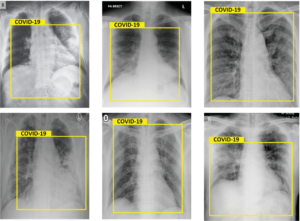

AI in Diagnosis, Telemedicine and Monitoring: AI-Powered COVID-19 Surveillance Solutions

Beyond the AI-Powered COVID-19 Surveillance Solutions, AI also strengthened healthcare systems through:

- AI-assisted CT scan and X-ray interpretation